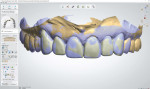

The scan of the temporary restorations was used as a guide to design the shape, form, and position of the final all-ceramic restorations as well as to evaluate different layering textures to create translucency and add characterization (Figure 6). Once completed, the final design was imported into the CAD software's dynamic virtual articulator for a functional evaluation.